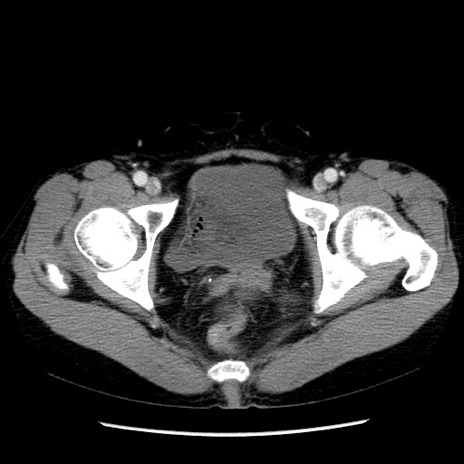

症例6(横断像)

【症例】50歳代女性

【主訴】下腹部痛

【現病歴】本日朝より下痢2回あり。 昼食を食べた後、嘔吐3回、下腹部痛認め、症状軽快せず、当院救急搬送。

最終食事:本日昼(生ものなし)。 昨日の夜、刺身を食ぺたとのこと。周囲に同様の症状の者なし。普段、排便は毎日あるとのこと。

【既往歴】卵巣癌術後(8年前に当院で卵巣摘出)

【身体所見】 意識清明、腹部:平坦、腸蠕動音→、やや硬、下腹部自発痛・圧痛あり、反跳痛あり、筋性防御なし。

【データ】WBC 16000、CRP 0.01